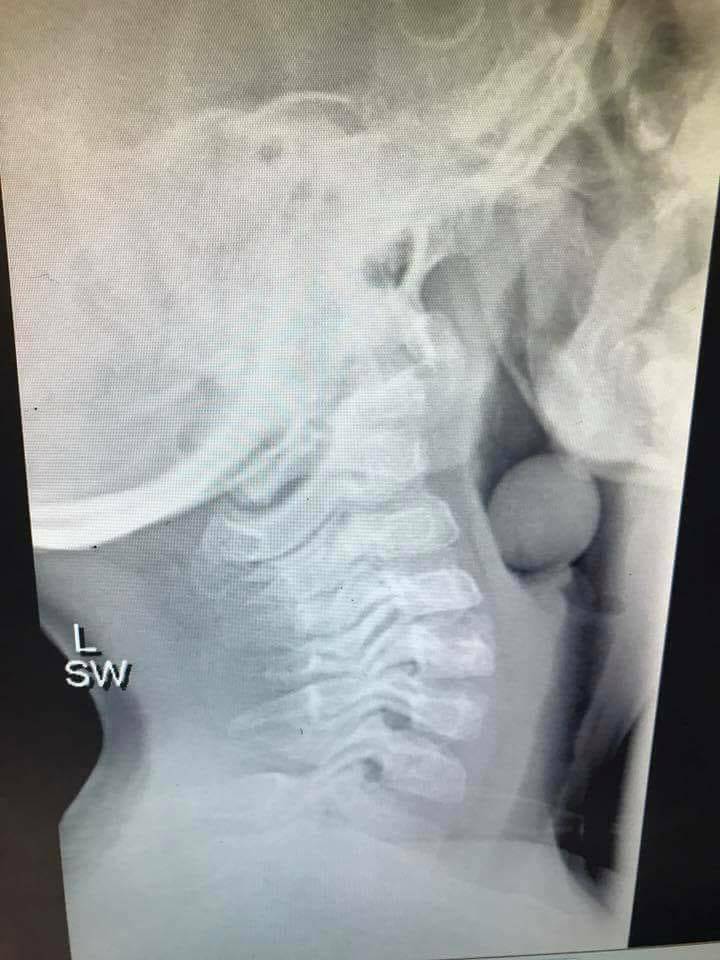

La mamma del piccolo ha accettato che il suo pediatra condividesse su Facebook la radiografia di un acino d’uva che si è incastrato nella gola di sua figlio. Per fortuna il piccolo – operato – ora sta bene, ma ha corso un grave pericolo.

Sapete cosa mostra questa radiografia? Un chicco d’uva!

Un chicco d’uva che si è posizionato all’inizio delle vie aeree di un bambino di 5 anni oggi.

Questa piccola anima è stata operata, sotto anestesia generale, per rimuovere il chicco.

E’ stato molto fortunato che parte delle sue vie aeree fosse aperta altrimenti sarebbe potuta finire male.